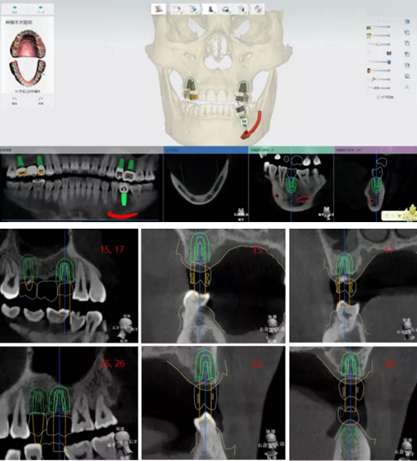

植體植入設(shè)計(jì)

設(shè)計(jì)植入5顆種植體

查看種植體螺絲通道穿出虛擬修復(fù)體的位置。

查看種植體在牙槽嵴頂穿出位置。

規(guī)劃種植導(dǎo)板

完成導(dǎo)板設(shè)計(jì)